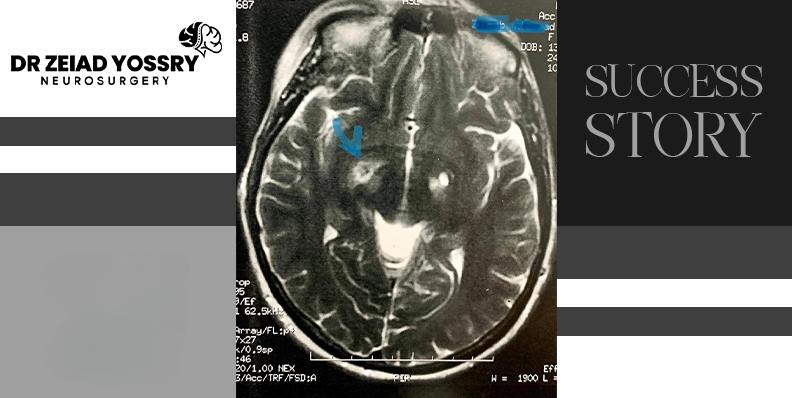

Dr. Zeiad Yossry performed basal ganglion ablation surgery, which involves targeting the globus pallidus. This area is responsible for the symptoms of Parkinson's disease. The surgery reduces its activity, helping to reduce tremors and slow movement symptoms. During the procedure, the medical team placed a frame to stabilize her head, and Dr. Zeiad Yossry determined a precise path using CT scans. After sterilizing the scalp, he made a tiny incision to insert electrodes used to stimulate the brain and monitor changes in symptoms. Once reaching the target area, Dr. Zeiad Yossry applied precise thermal energy to ablate the basal ganglion. Finally, he performed an MRI scan to confirm successful symptom control.